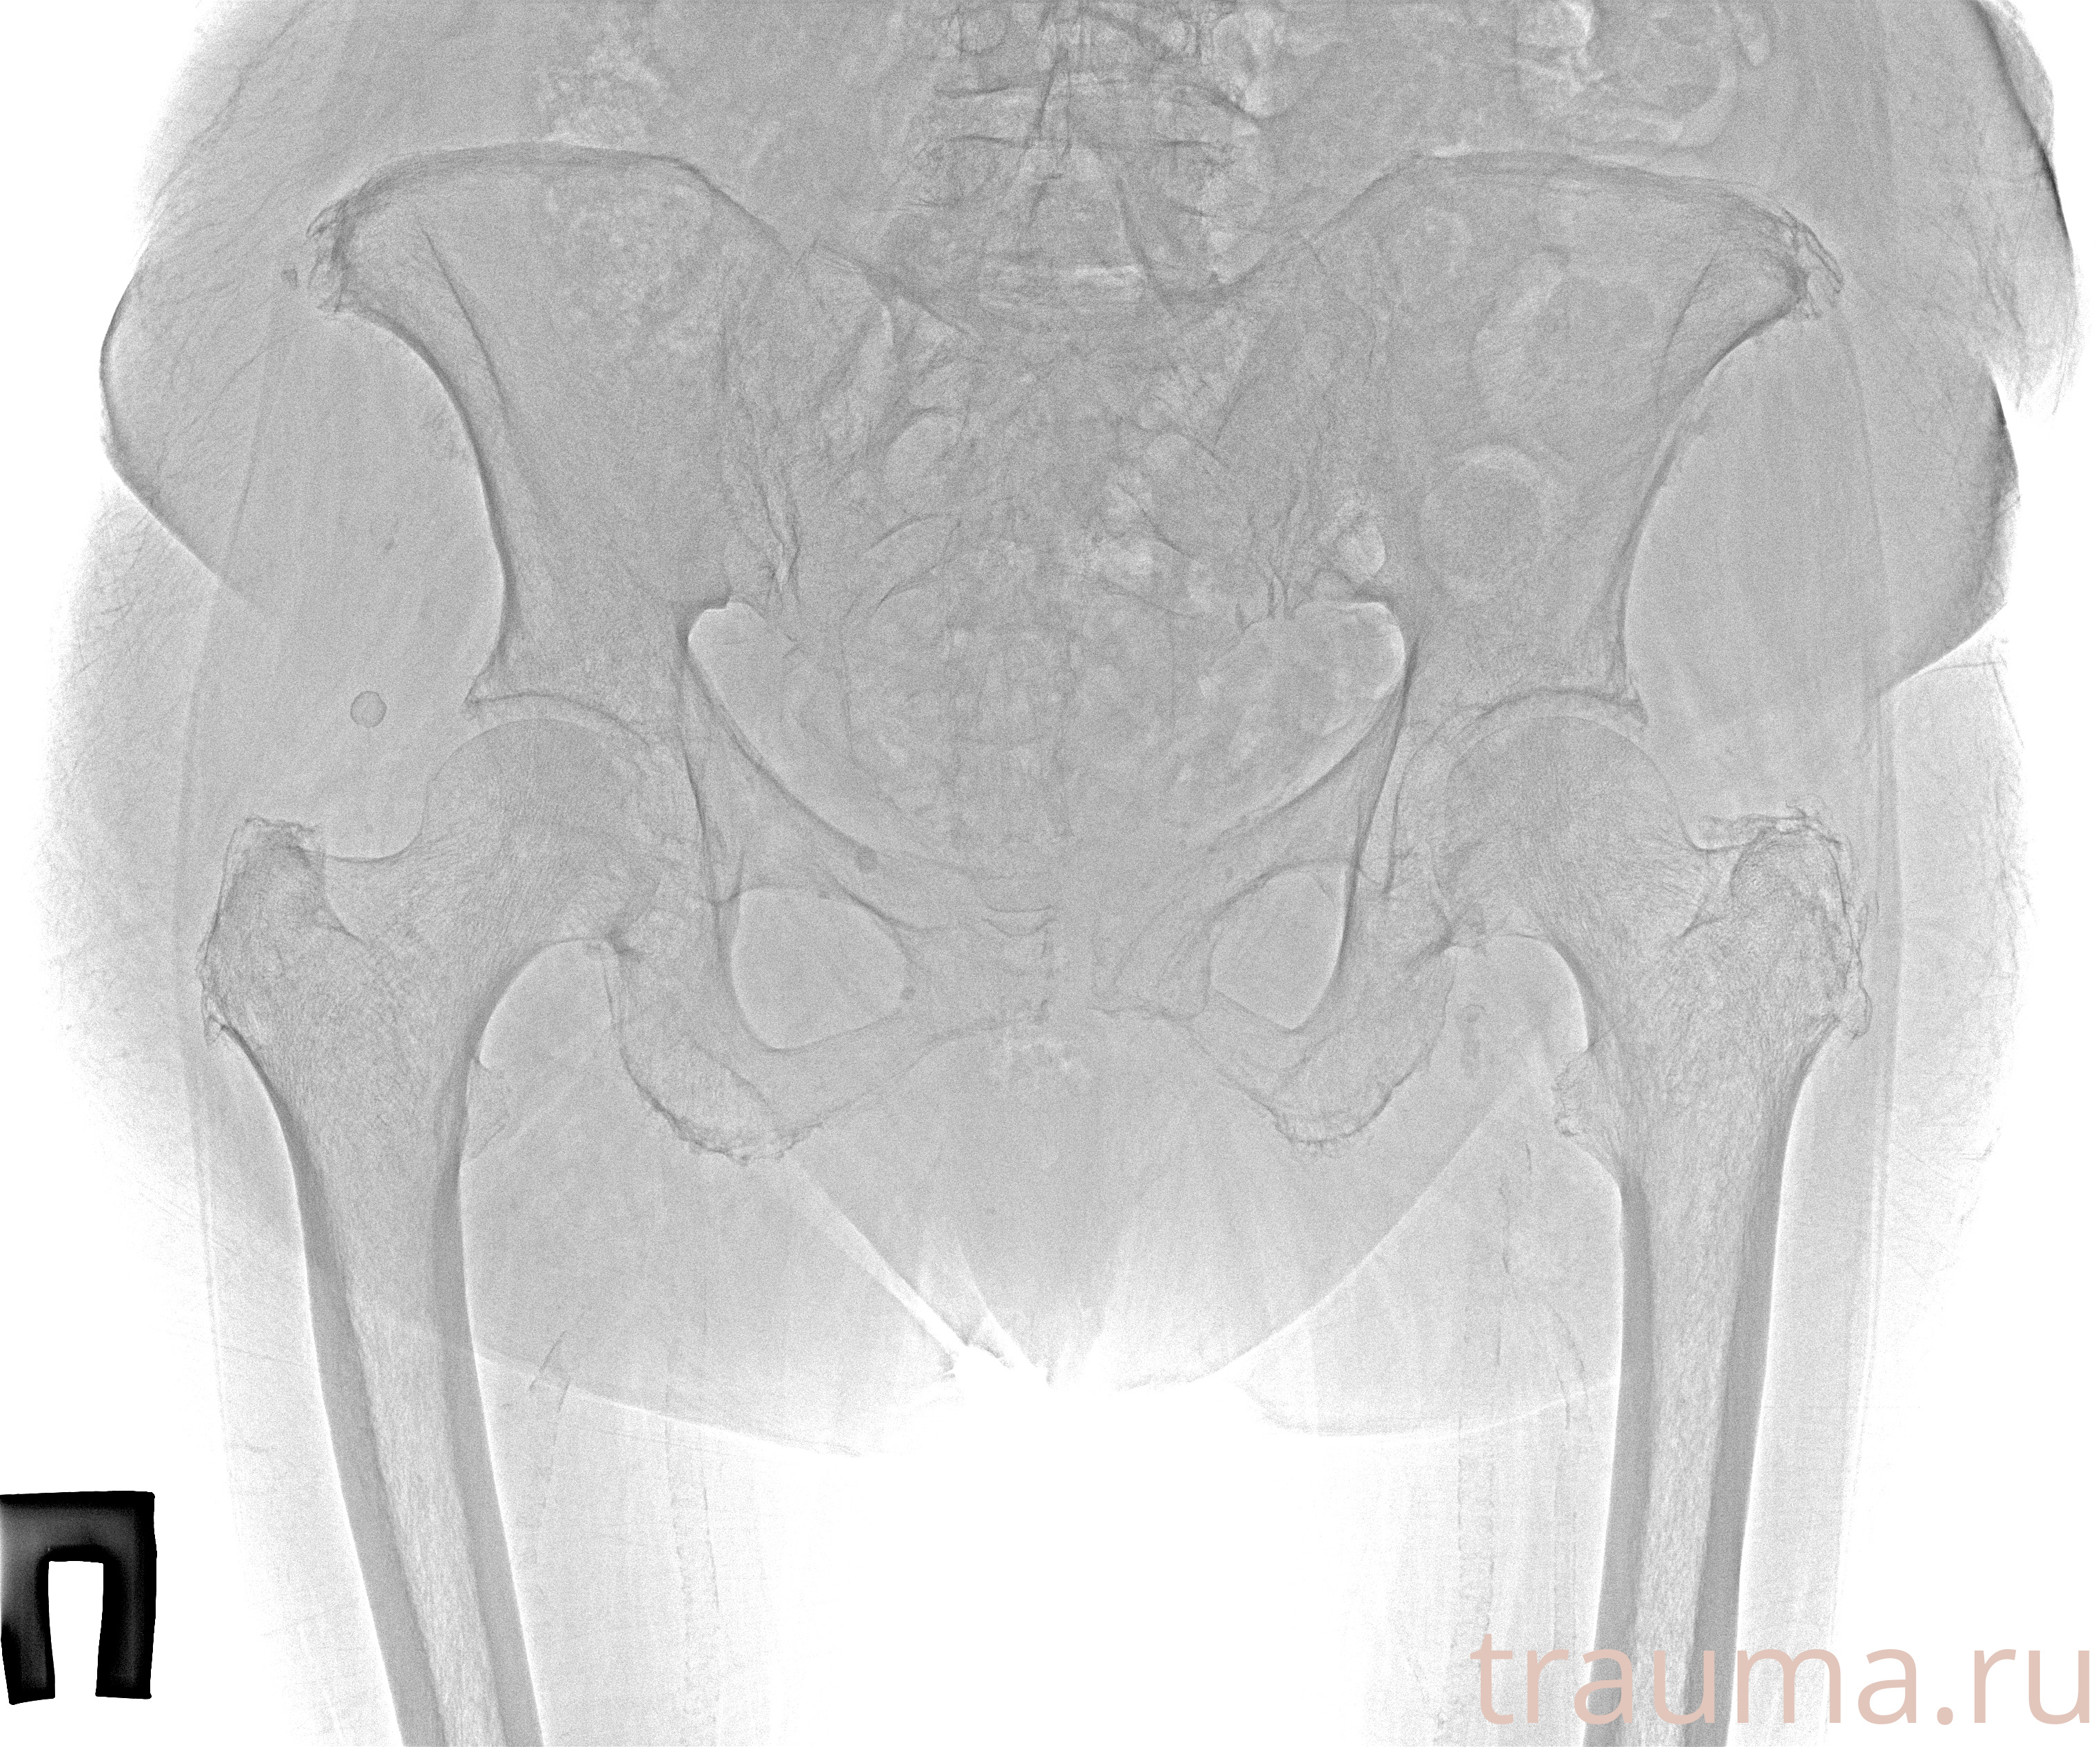

Рентгенограммы